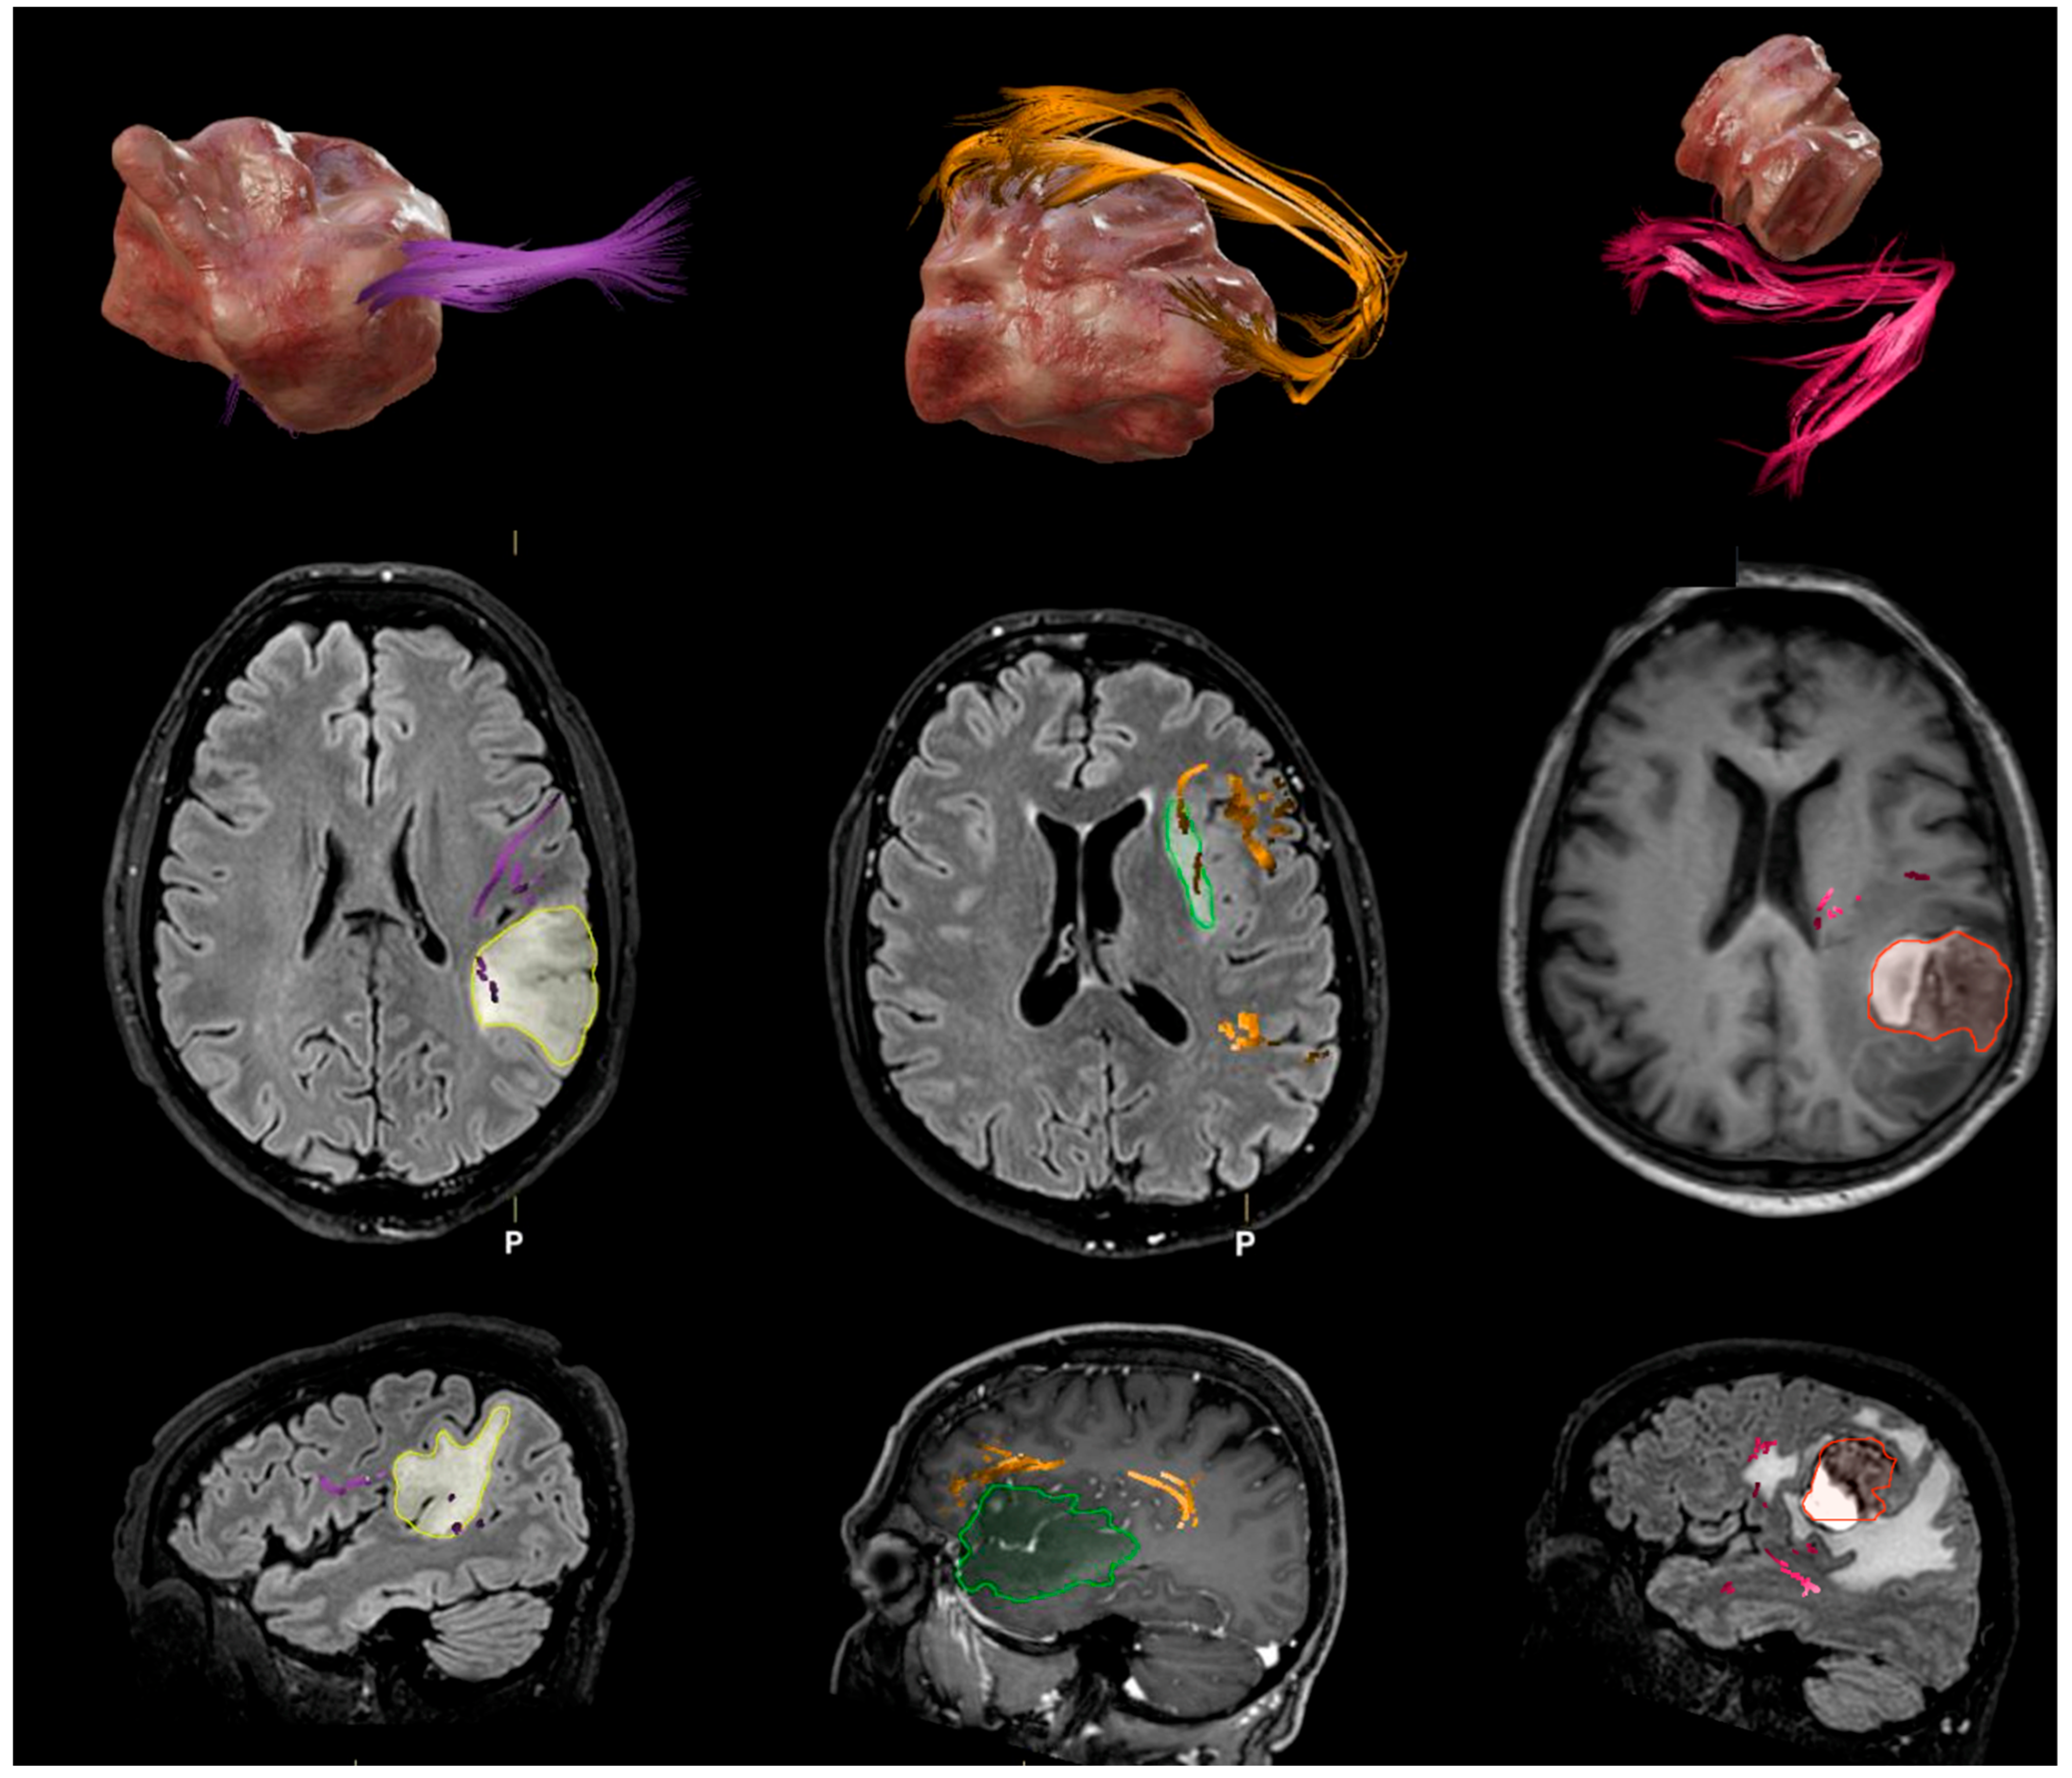

- Altieri, R.; Melcarne, A.; Junemann, C.; Zeppa, P.; Zenga, F.; Garbossa, D.; Certo, F.; Barbagallo, G. Inferior Fronto-Occipital Fascicle Anatomy in Brain Tumor Surgeries: From Anatomy Lab to Surgical Theater. J. Clin. Neurosci. 2019, 68, 290–294. [Google Scholar] [CrossRef]

- Altieri, R.; Bianconi, A.; Caneva, S.; Cirillo, G.; Cofano, F.; Corvino, S.; de Divitiis, O.; Pepa, G.M.D.; De Luca, C.; Fiaschi, P.; et al. Quantitative Evaluation of Neuroradiological and Morphometric Alteration of Inferior Fronto-Occipital Fascicle across Different Brain Tumor Histotype: An Italian Multicentric Study. Acta Neurochir. 2025, 167, 71. [Google Scholar] [CrossRef]